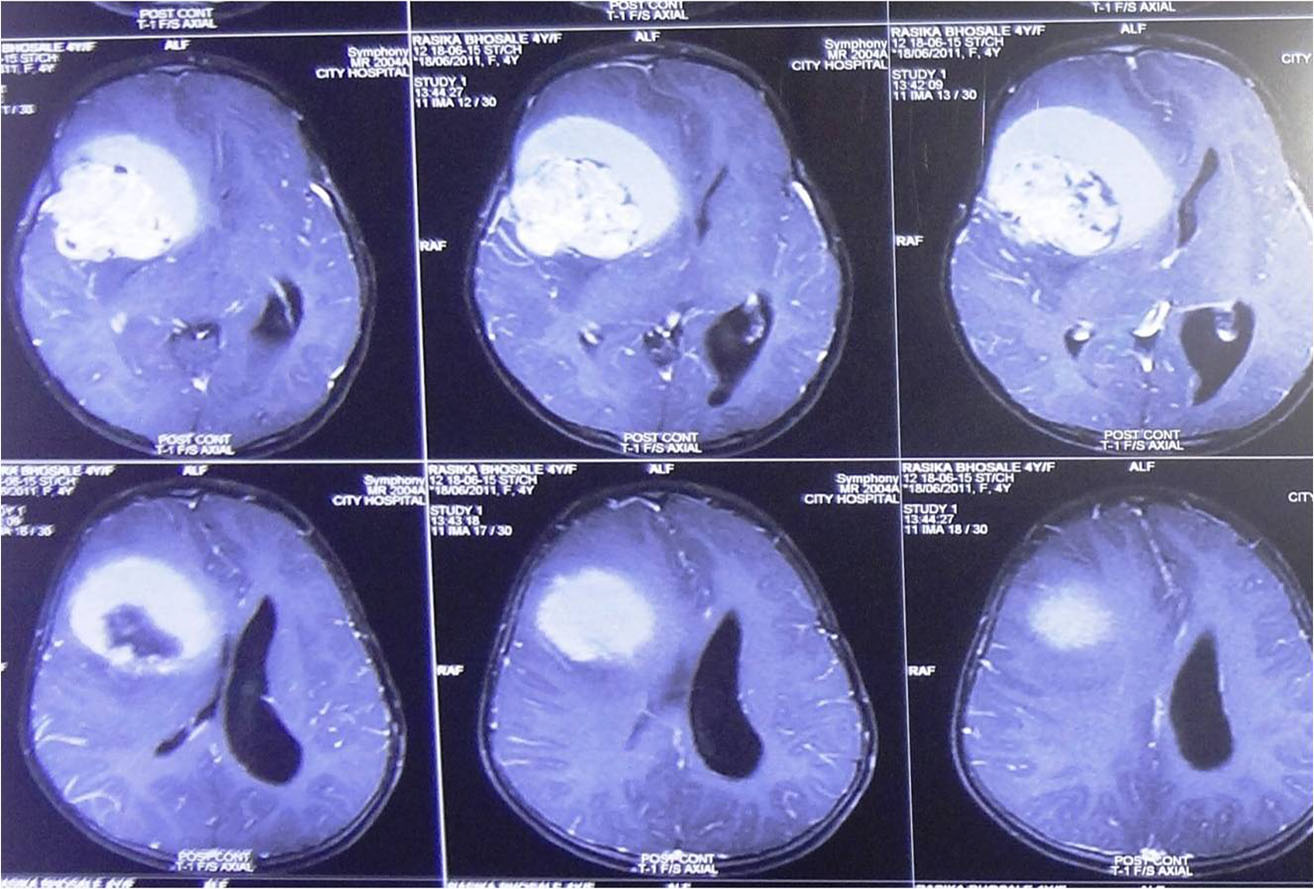

Traumatic Brain injury is defined as damage to the brain resulting from external mechanical force,

commonest causes of brain injury are vehicular accidents, assaults, and accidental falls etc.

Brain injuries can be minor or major life threatening. The signs and symptoms depend on the severity of injury.

It is important to begin emergency treatment within the so-called "Golden Hour" following the injury.

Minor injuries are usually treated with medications and constant monitoring. Moderate to severe injuries require treatment in neurosurgical ICU and may require emergency surgery.